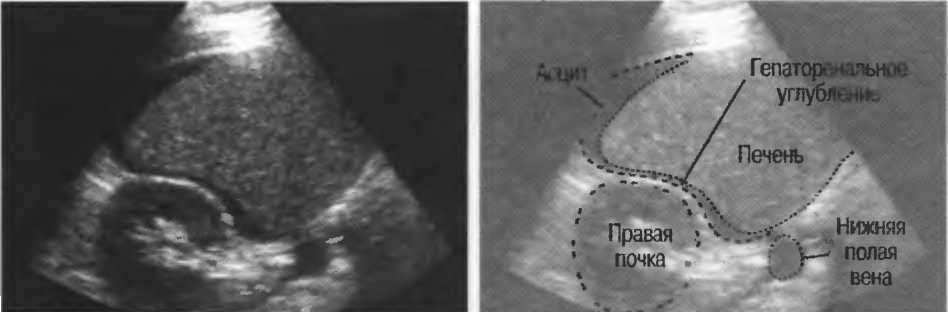

1. Подготовка

Пациент не должен пить и есть в течение 8 ч перед исследованием. Если жидкость необходима для предотвращения дегидратации, можно давать пациенту только воду. При острой симптоматике исследование можно проводить без подготовки. Детям, если позволяют клинические условия, пища и вода не даются в течение 3 ч до исследования.

При более углубленном исследовании, если нет клинических противопоказаний, может быть полезным дополнительный прием воды, особенно при исследовании поджелудочной железы, нижних отделов живота и таза.

2. Положение пациента. Пациент может лежать в удобной позе на спине. Под голову можно положить маленькую подушку, в случае выраженного напряжения передней брюшной стенки подушечку можно поместить также под колени пациента.

Намажьте живот гелем.

Пациенту разрешается дышать спокойно, однако при исследовании отдельных органов требуется задержка дыхания на вдохе.

3. Выбор датчика. Используйте датчик 3,5 МГц для взрослых и датчик 5 МГц для детей и худых взрослых. Предпочтительны конвексные или секторные датчики.

4. Установите правильный уровень общей чувствительности. Начинайте исследования, поместив датчик центрально в верхней части живота под мечевидным отростком и попросите пациента глубоко вдохнуть и задержать дыхание на вдохе.

Поверните датчик направо до того, как начнет визуализироваться печень. Отрегулируйте чувствительность, чтобы изображение имело нормальную однородную зхоструктуру. Должна быть хорошо различима высокоэхогенная линия диафрагмы сразу за задними отделами печени (рис. 27а).

Воротная и печеночные вены должны визуализироваться как трубчатые структуры с анзхогенным просветом. Стенки воротной вены высокозхогенны, но стенки печеночных вен практически не видны (рис. 276).

Рис.27а. Продольный срез. Неизмененная печень и диафрагма.